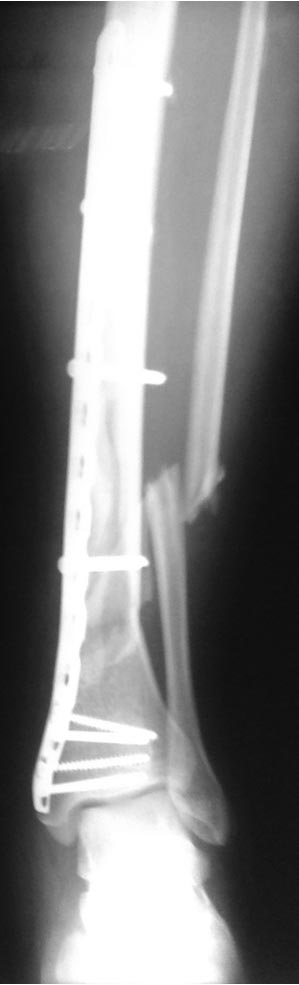

[Ortho] Деформация фиксатора после падения

первичные снимки и остальные качеством получше.

Имя     : AP.jpg

Тип     : image/jpg

Размер  : 29104 байтов

Url     : http://weborto.net:8080/pipermail/ortho/attachments/20121105/5ddbb42f/attachment-0007.jpg